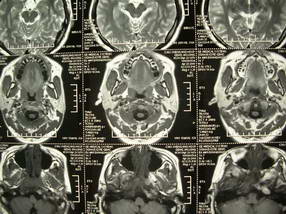

扫描示鼻咽腔不对称,中度狭窄,右侧咽隐窝消失,局部软组织肿块,鼻咽右侧壁增厚形成肿块,突入鼻咽腔,肿块平扫呈等密度,肿块向深部侵润,右侧翼内外肌受侵,右侧咽旁间隙变窄;向后生长,头长肌界线欠清,向后上生长侵犯同侧颈动脉鞘区。双侧海绵窦增宽,内见软组织影与鼻咽部肿块相连。考虑鼻咽癌。鼻咽癌主要是放射治疗,且效果较好;到当地有治疗设备较大医院治疗即可。

鼻咽部新生物(纤维血管瘤?鼻咽癌?)侵犯右侧中颅窝底及右侧海绵窦;建议必要时活检定性。

鼻咽部新生物侵犯右侧中颅窝底及右侧海绵窦,鼻咽癌可能性大。建议增强扫描。纤维血管瘤禁忌穿刺。